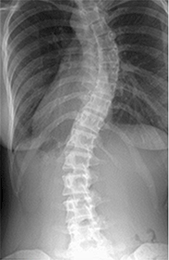

• 측정 범위

X-ray 소스를 통한 Spine, Pelvis, Leg의 Radiography를 획득시 신속하고 정확하며 만곡 및 수평정도의 Data를 쉽게 얻을 수 있으며 환자의 진료에 필요한 자세한 정보를 얻게 됩니다.

• 측만증 정보

SOCLIO의 Lead Line이 척추의 휨 정도를 쉽게 판단할 수 있도록 하며 Radiography에 도출될 수 있도록 Lead Line이 폭넓게 분포되어 있습니다. 또한 2, 3장으로 분할 획득한 영상을 쉽게 조합 가능하며 정밀한 하나의 Spine 이미지를 얻을수 있습니다.

• 골반 정보

SCOLIO를 이용한 골반의 수평정도를 알 수 있습니다.